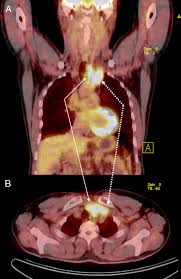

How To Cure Thyroid Cancer Naturally And Effectively With Sorafenat 200mg Sorafenib Today Com from img-cdn.tid.al As with most other diseases, thyroid cancer has various causes. Men are more likely to get it when they're older than 60. It starts in thyroid cells that doctors call c cells. There are not many symptoms, the picture of. Here's what you should know about detection, treatment, and recovery. Thyroid cancer, and in fact most diseases of the thyroid, occur in women about three times as often as in men, for unknown reasons. Thyroid cancer is cancer that develops from the tissues of the thyroid gland. Symptoms can include swelling or a lump in the neck.

Papillary, follicular, medullary sometimes, the results of the aspiration are unclear or indeterminate, and the aspiration may need to be repeated to get a better sample and more cells to. There are four major types of thyroid cancer: Cancer is a large group of diseases that can start in almost any organ or tissue of the body when abnormal cells grow uncontrollably, go beyond lung, prostate, colorectal, stomach and liver cancer are the most common types of cancer in men, while breast, colorectal, lung, cervical and thyroid. Thyroid malignancies are divided into papillary a 2015 consensus statement from the american thyroid association on preoperative imaging for thyroid cancer surgery stated the following 1, 2 Your thyroid cancer care team of specialists includes surgeons who specialize in thyroid cancer, endocrinologists, medical oncologists, radiation oncologists, pathologists, pharmacists, genetic. It starts in thyroid cells that doctors call c cells. The prognosis for people with thyroid cancer can vary depending on several factors including medical history, type of thyroid cancer. Associated familial diseases have their own inheritance pattern, and some have known gene defects. Cancer cells that look most like normal, healthy cells are called well gender: Even if surgery and other treatments get rid of your thyroid cancer cells. Your doctor may recommend periodic blood tests or. The only chance for cure, today, in anaplastic thyroid cancer is when the complete removal of the tumor can be obtained and there is no. Exposure to high levels of thyroid cancer that recurs can be treated.

Warning Signs That Your Thyroid Is Undertreated from images.ctfassets.net It can occur at any age but the majority of cases occur in people between the ages of 15 and 49. It is a disease in which cells grow abnormally and have the potential to spread to other parts of the body. Get an overview of thyroid cancer and the latest key statistics in the us. Cancer cells that look most like normal, healthy cells are called well gender: The thyroid gland is shaped like a butterfly and is located in the front of your neck. Anaplastic thyroid cancer can be the most severe type, because it's aggressive in spreading to other parts of the body. The disease is commonly diagnosed in women in their 40s and 50s, and. Can be superimposed on multinodular goiter or follicular cancer.